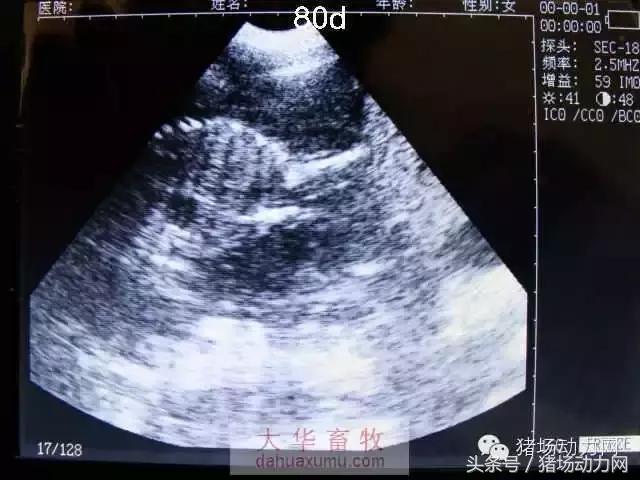

以下为怀孕母猪21天到90天之内的变化图:

80天